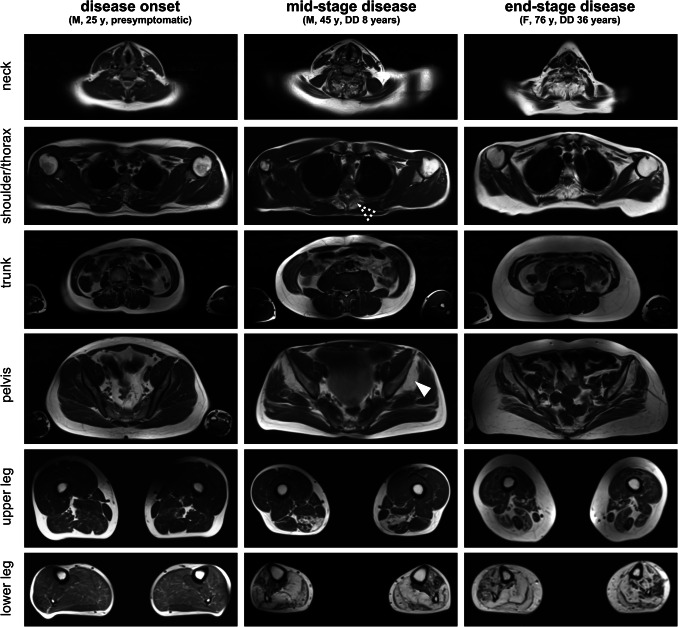

Muscular involvement was mainly symmetrical. A predominant affection of the lower extremities with an emphasis on the lower legs was observed. In lower legs, a predominant involution of soleus muscle as well as medial head of gastrocnemius muscle was detected. However, the anterior and lateral compartment (e.g. tibialis anterior, extensor digitorum longus and peroneus longus muscle) were also involved in most of the cases, though to a lesser extent. A variable degeneration of lateral head of gastrocnemius muscle was seen. However, the deep posterior compartment was mainly unaffected. In thighs, a selective affection of parts of the hamstring muscles (semimembranosus muscle and the long head of the biceps femoris muscle) was observed whereas the anterior and medial compartments were mostly spared. Imaging of the trunk showed early and severe involvement of the gluteus minimus muscle. In contrast, gluteus medius muscle showed a variable grade of affection while gluteus maximus muscle appeared to be not relevantly involved. Evaluation of the paraspinal musculature revealed a scattered degeneration predominantly affecting thoracic parts of the axial musculature (e.g. thoracis longus, semispinalis thoracis and spinalis thoracis muscles). The cervical and lumbar parts of paraspinal musculature appeared only mildly affected. Except for the deltoid muscle, that—especially in the ventral part—showed a moderate involution, no relevant involvement of the musculature of shoulder and arm was seen. Representative examples of whole body imaging findings in MATR3-myopathy are depicted in Fig. 1 while the observed grade of alteration for the individual muscles as determined by Fischer grading are shown in Fig. 2.

Fig. 1.

Magnetic resonance imaging in MATR3-associated distal myopathy. Representative T1-weighted MRI slices of head/neck, shoulder/thorax, trunk, pelvis, upper and lower leg in patients with different disease stages of MATR3-associated distal myopathy. Note the early affection of gluteus minimus muscle (white arrowhead) and thoracic segments of paraspinal musculature (dashed arrowhead) while gluteus medius and maximus muscles as well as cervical and lumbar segments of paraspinal musculature are relatively spared. DD disease duration, y years, F female, M male